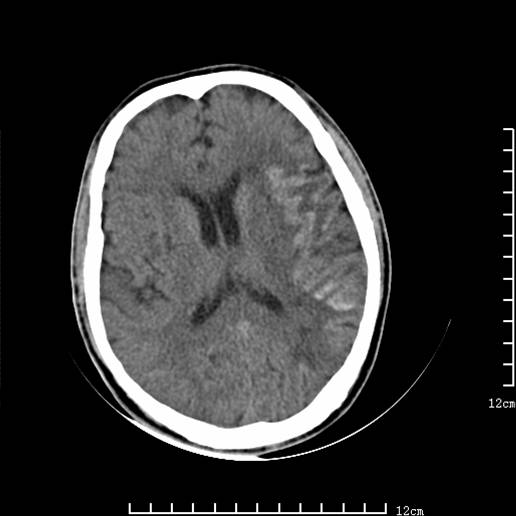

以下图像分别是3月25日凌晨及下午图像、3月27日、4月16日的ct图像。

4月16日

4月16日ct复查:符合出血性脑梗塞表现。

资料齐全,符合脑梗塞溶栓治疗后,血管再通而致的出血性脑梗塞。

支持出血性脑梗塞,可能因血管再通后,再灌注损伤所致。

4月16日ct复查:符合出血性脑梗塞表现